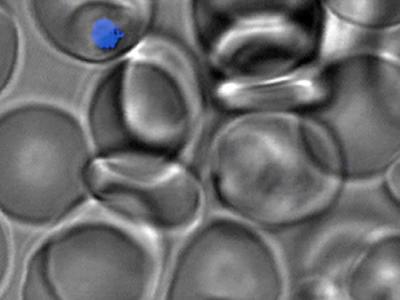

显微镜图像展示了T3.5如何存在于将红血球感染的疟原虫中。 你可以将其称为一种治...